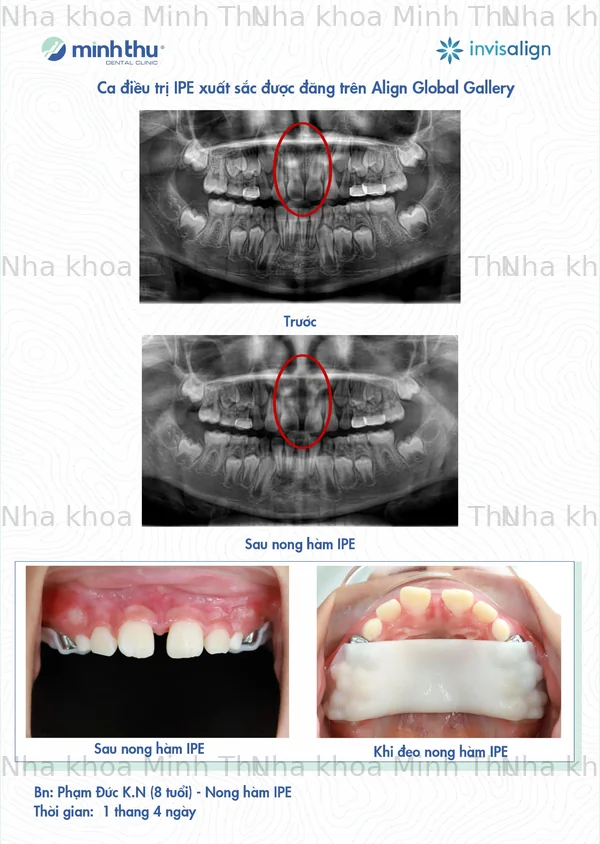

Bác sĩ Vũ Đức Tùng vừa có ca điều trị xuất sắc IPE thứ 9 được đăng trên Align Global Gallery

Một số ca nong hàm IPE tại Nha Khoa Minh Thu, kết quả phụ thuộc vào tình trạng và mức độ đáp ứng điều trị của mỗi bệnh nhân.